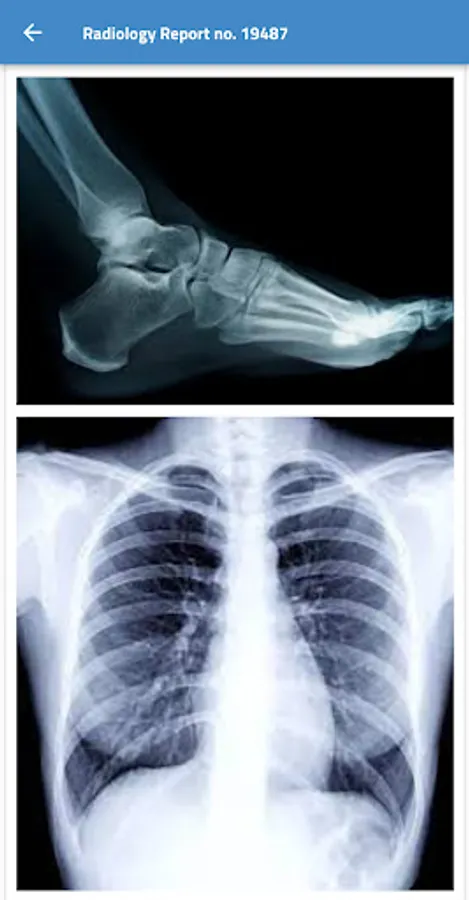

microcare Screenshots